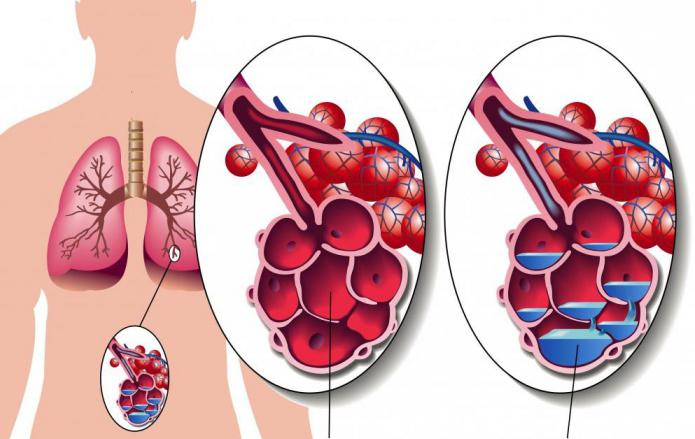

В основе патологического механизма развития основную роль играют нарушения проницаемости мембраны между альвеолами и капиллярами, снижение коллоидно-осмотического и увеличение гидростатического давления в сосудах микроциркуляторного русла.

В начальной стадии происходит пропотевание транссудата в интерстициальную легочную ткань. Избыточное его накопление и обуславливает развитие сердечной астмы (интерстициального отека легких).

Дальнейшее нарастание отечности тканей способствует проникновению транссудата в полость альвеол, где он смешивается с воздухом с образованием пены. Эта пена и препятствует нормальному газообмену. Данная стадия называется альвеолярным отеком.

В этот момент происходит активное наполнение капилляров кровью и быстрым прохождением жидкости через стенки капилляров в альвеолы, где ее собирается так много, что это сильно затрудняет поступление кислорода. В органах дыхания нарушается газообмен, клетки тканей испытывают острую недостаточность кислорода (гипоксия), человек задыхается. Нередко удушье случается ночью во время сна.